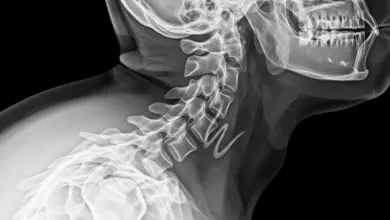

Exames que confirmam

O caminho começa com história clínica e exame físico detalhados. Em seguida, os exames de imagem definem o grau e estabilidade.

- Radiografias AP e perfil, com medidas de Meyerding e dos ângulos.

- Radiografias dinâmicas em flexão e extensão, para avaliar a instabilidade.

- Ressonância magnética, para observar o disco, facetas, canal e raízes.

- Tomografia, útil em dúvidas anatômicas e planejamento cirúrgico.